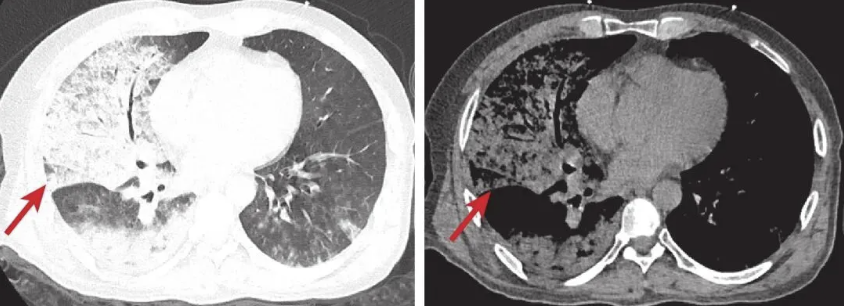

胸部CT(图1):双肺弥漫性大片状实变影,内见支气管充气征。病情严重度评分:CURB65评分:4分,急性生理学与慢性健康状况评分II(APACHE II) :32分,序贯器官衰竭评分(SOFA) :18分。

图1 入院时胸部CT检查图像

双肺多发大片状密度增高影,部分融合实变,可见支气管充气征(箭头所示)。